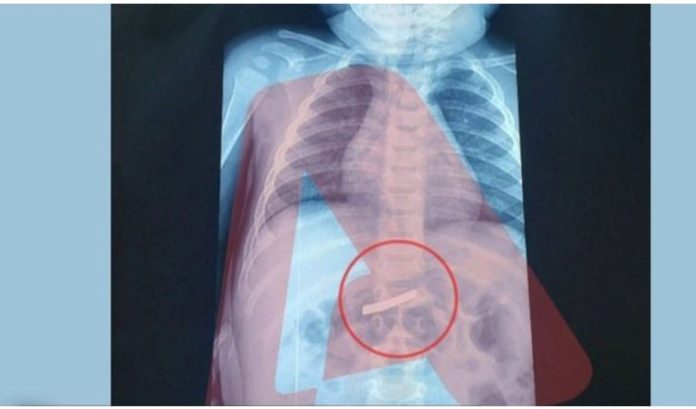

Ένα σοβαρό περιστατικό καταγράφηκε το πρωί της Τετάρτης (18/3), όταν ένα παιδί τριών ετών μεταφέρθηκε εσπευσμένα στο νοσοκομείο Παίδων, στην Αθήνα, έχοντας καταπιεί ένα ξυραφάκι.

Ειδικότερα, σύμφωνα με ρεπορτάζ που μεταδόθηκε από τον Alpha, οι γονείς του παιδιού ενημέρωσαν το ιατρικό προσωπικό κατά την άφιξή τους ότι το παιδί είχε καταπιεί το αιχμηρό αντικείμενο, γεγονός που κινητοποίησε άμεσα τους ιατρούς.

Πραγματοποιήθηκε άμεσα ακτινογραφικός έλεγχος, ώστε να αξιολογηθεί η κατάσταση και στη συνέχεια το παιδί οδηγήθηκε στο χειρουργείο και υπεβλήθη σε επέμβαση. Σύμφωνα με το ρεπορτάζ, η επέμβαση ήταν επιτυχής και το παιδί έχει πλέον διαφύγει τον κίνδυνο.